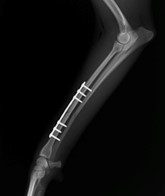

眼球摘出、眼瞼腫瘤切除、チェリーアイ整復、眼瞼縫合、瞬膜フラップ、眼球突出整復、耳介切除、垂直耳道切除、総耳道切除、鼻鏡切除、口腔腫瘍切除(上顎骨切除、下顎骨切除を含む)、各種抜歯(猫の全臼歯抜歯含む)舌腫瘍切除、唾液腺嚢胞切除、皮膚腫瘤切除、断脚(前肢、後肢、片側骨盤切除)、断尾、肺葉切除、胸腺腫切除、心膜切除、横隔膜ヘルニア整復、肝臓腫瘍切除、胆嚢摘出、胃切開、胃拡張胃捻転症候群整復、胃腫瘍切除、腸管切開、腸管腫瘍切除、直腸腫瘍切除(粘膜、全層プルスルーなど)、腎臓摘出、SUB設置手術、脾臓摘出、副腎摘出、膀胱切開、膀胱腫瘍切除(部分切除、全摘出、膀胱尿道一括切除など)、卵巣腫瘍切除、精巣腫瘍切除、卵巣子宮全摘出、肛門嚢切除、各種骨折、膝蓋骨脱臼整復、股関節脱臼整復、大腿骨頭切除、椎間板ヘルニア(各種椎弓切除術)、各種リンパ節切除 など